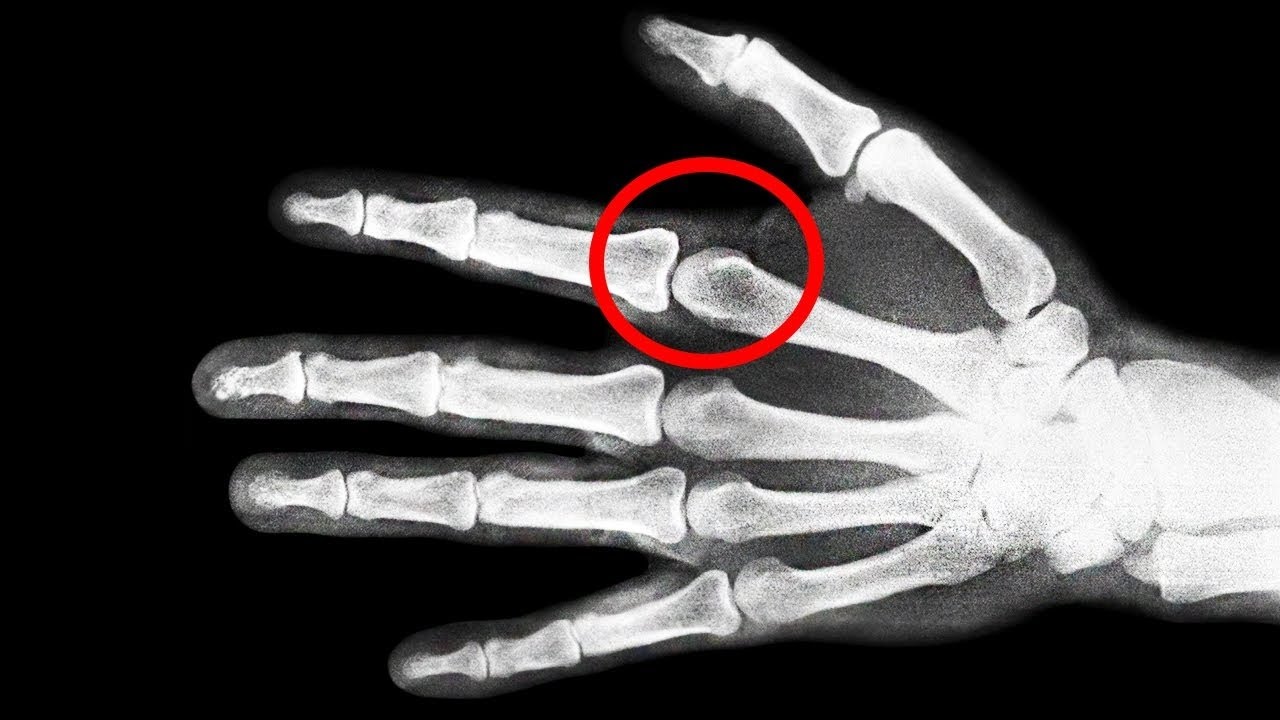

Probablemente eres parte del porcentaje de personas que a diario se crujen los dedos, y quizá, en mas de una ocasión te hayas preguntado si realmente hacerlo es malo o no para tus nudillos... En este video te hablaré de si es MALO crujirse los huesos de tus manos, y por ende, espero que tus dudas se resuelvan...

¿Es MALO Crujirse Los Dedos? ─ Mr. Tops